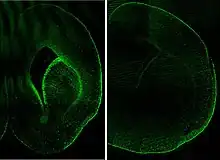

FABP7 is expressed, during development, in radial glia by the activation of Notch receptors.[6] Reelin was shown to induce FABP7 expression in neural progenitor cells via Notch-1 activation.[7]

As of 2008, two studies have been conducted into FABP7 as a possible risk gene for schizophrenia,[10] with one, that tested for only one SNP, showing negative[11] and another, with seven SNPs,[12] a positive result. The effect of the gene in the latter study was stronger in males. This study also linked FABP7 variation to weak prepulse inhibition in mice; deficit in PPI is an endophenotypic trait observed in schizophrenia patients and their relatives.